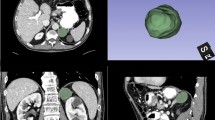

After 2 or more years of stability (ranging from 2 to 5 years), the incidence of SSN growth was only 5% (95% CI: 3–7%) [3, 7,8,9,10, 17, 19, 20, 22]. The heterogeneity of this analysis was lower than that of the overall analysis (Q = 35.40, p < 0.01, I2 = 77.00% vs. Q = 425.35, p < 0.001, I2 = 97.83%) (Figs. 2 and 3). Another subgroup analysis based on the initial mean/median diameter of SSNs was conducted (Table E2 and Fig. 3b). When we removed the study with an initial mean/median diameter < 5 mm [3] for subgroup analysis, there was no heterogeneity in the subsequent analysis (Q = 8.22, p = 0.31, I2 = 15.00%). The incidence of growth after 2 years of stability or more for SSNs with an initial diameter ≥ 5 mm was 4% (95% CI: 3–5%) (Fig. 3b). Patient examples of stable and growing SSNs after long-term follow-up are shown in Figs. 4 and 5, respectively.

Forest plot of the incidence of subsolid nodule growth after 2 years of stability or more (a) and forest plot of the incidence of subsolid nodule growth after 2 years of stability or more for the subgroup analysis for SSNs ≥ 5 mm and < 5 mm (b). Diameter: the initial mean/median diameter of the SSNs